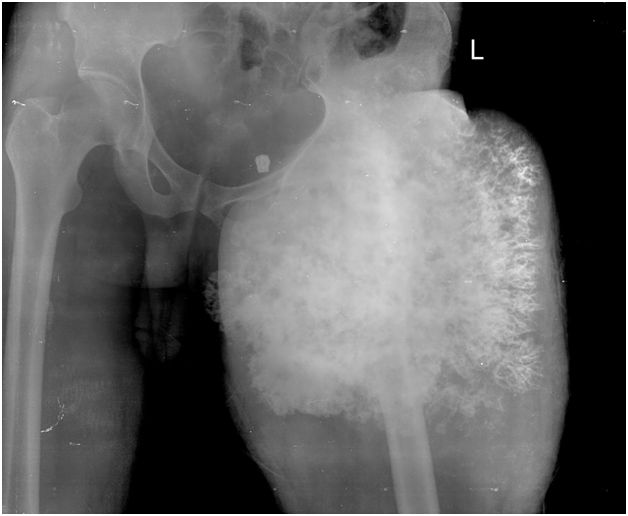

55-year-old male with swelling in left leg for four months.